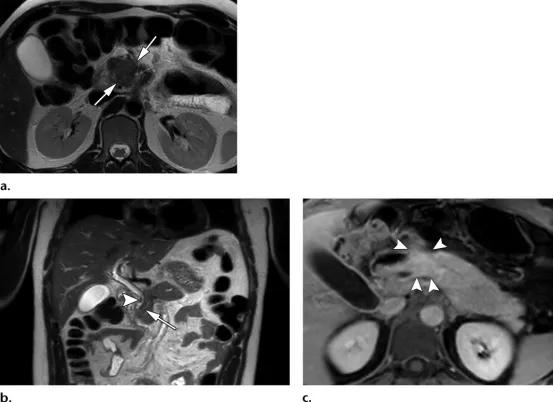

42岁男性,2型自身免疫性胰腺炎

(a图)轴位T2WI示胰腺近端边界不清的等信号肿块样病变(白色长箭头)

(b图)冠状位T2WI示胰管管径变窄,并横穿同一区域(白色长箭头),关注视察胆总管远端的局灶性狭窄(白色短箭头)

(c图)轴位增强延迟期磁共振示同一区域的局灶性肿物样病变(白色短箭头),其余胰腺未见明确异常。

35岁女性,1型自身免疫性胰腺炎,(a图)轴位T2WI示低信号纤维化边缘(白色长箭头),(b图)轴位增强磁共振示均匀强化的胰腺以及不强化的纤维边缘(白色长箭头)。